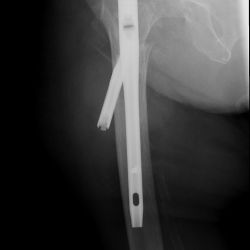

Schlecht festgeschraubt